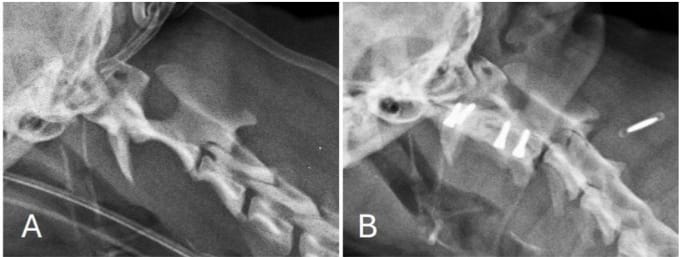

Lateral view of the cervical spine before (A) and after (B) surgical treatment. Correct screw insertion can also be observe